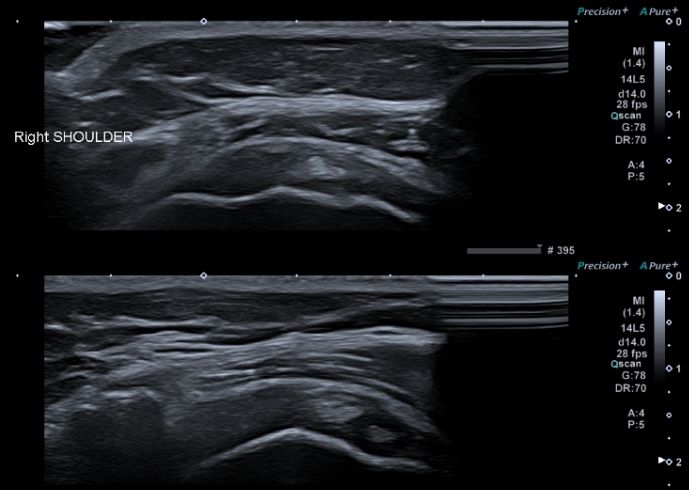

A ecografia osteoarticular utiliza ultra-sons de alta frequência emitidos por uma sonda, que atravessam os tecidos e são refletidos, formando imagens em tempo real das estruturas avaliadas.

Durante a ecografia, o(a) paciente é colocado(a) deitado(a) ou sentado(a), consoante a articulação a estudar. O exame é realizado numa sala pouco iluminada para facilitar a leitura das imagens. O médico aplica um gel transparente sobre a pele da região a avaliar, permitindo a correta transmissão dos ultra-sons e o deslizar da sonda.

As imagens são observadas em tempo real num ecrã e interpretadas pelo médico especialista. O exame pode durar entre 15 a 30 minutos, dependendo da articulação e da complexidade do caso.

A ecografia osteoarticular permite observar em detalhe as articulações e tecidos envolventes, sendo útil para identificar inflamações, derrames articulares ou alterações na membrana sinovial. É também capaz de detetar lesões musculares, ruturas ou degenerações de tendões e ligamentos, bursites e quistos. Através do Doppler, é possível avaliar o fluxo sanguíneo local, ajudando no diagnóstico de inflamações ativas.